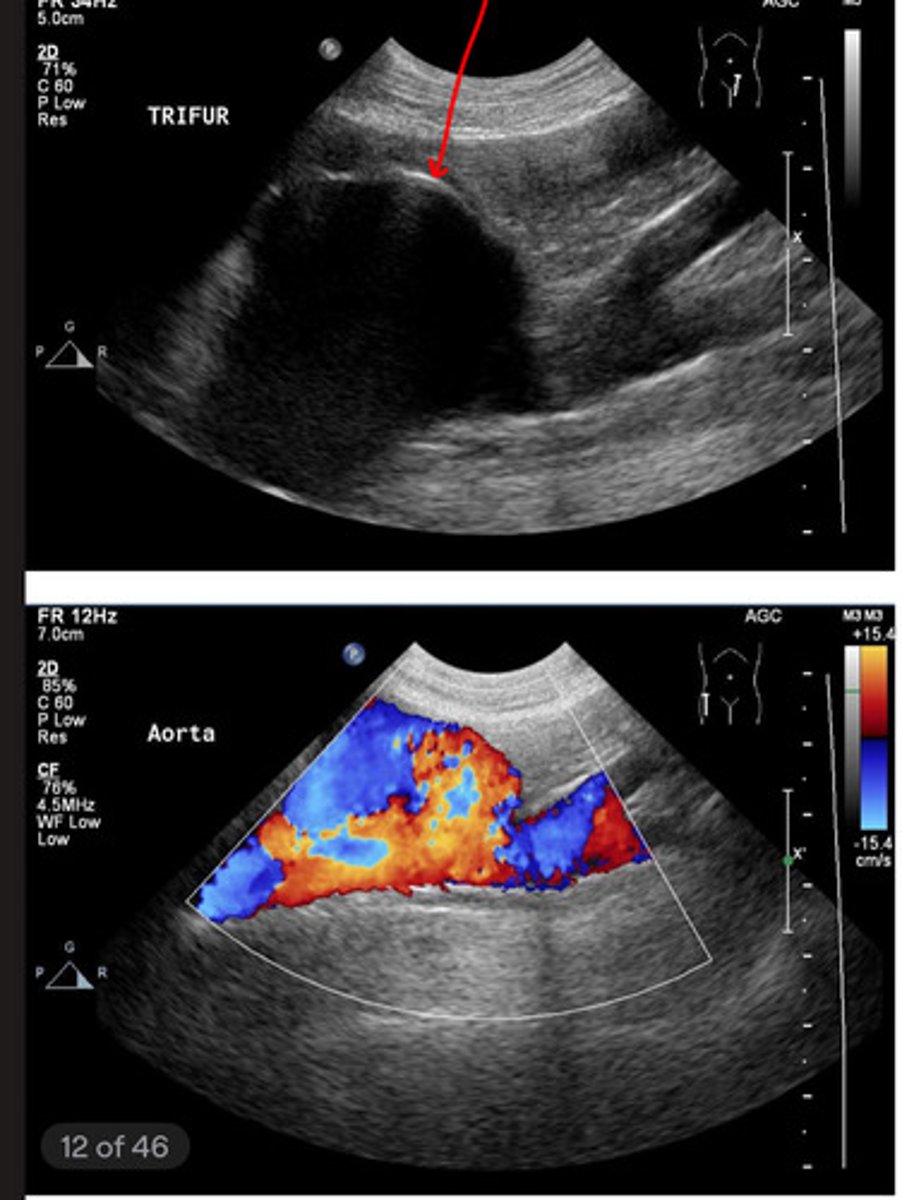

what are the arteries involved in the aorta trifurcation?

external iliac arteries

what arteries are the yellow arrows? (apart of the aortic trifurcation)

red- external iliac a.

blue- internal iliac a.

red- caudal vena cava

blue- aorta

what is the red and blue vasculature?